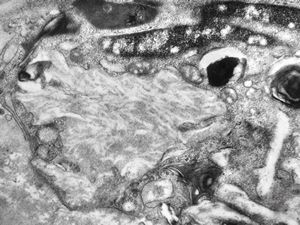

M,71y. | CADASIL accompanied with Alzheimer disease - brain vessel - arrows: granular osmiophilic material (GOM) between basement membranes

M,71y. | CADASIL accompanied with Alzheimer disease - brain vessel - arrows: granular osmiophilic material (GOM) between basement membranes

M,71y. | CADASIL accompanied with Alzheimer disease - brain vessel - arrow: granular osmiophilic material (GOM) in basement membrane